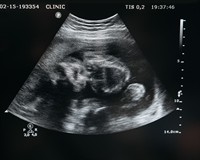

Вагітні жінки проходять ультрозвукове дослідження тричі, щоб оцінити стан розвитку плода, або частіше, за рекомендацією лікаря. Саме на УЗД майбутні мами можуть дізнатися про стать своєї дитини.

Знімок УЗД